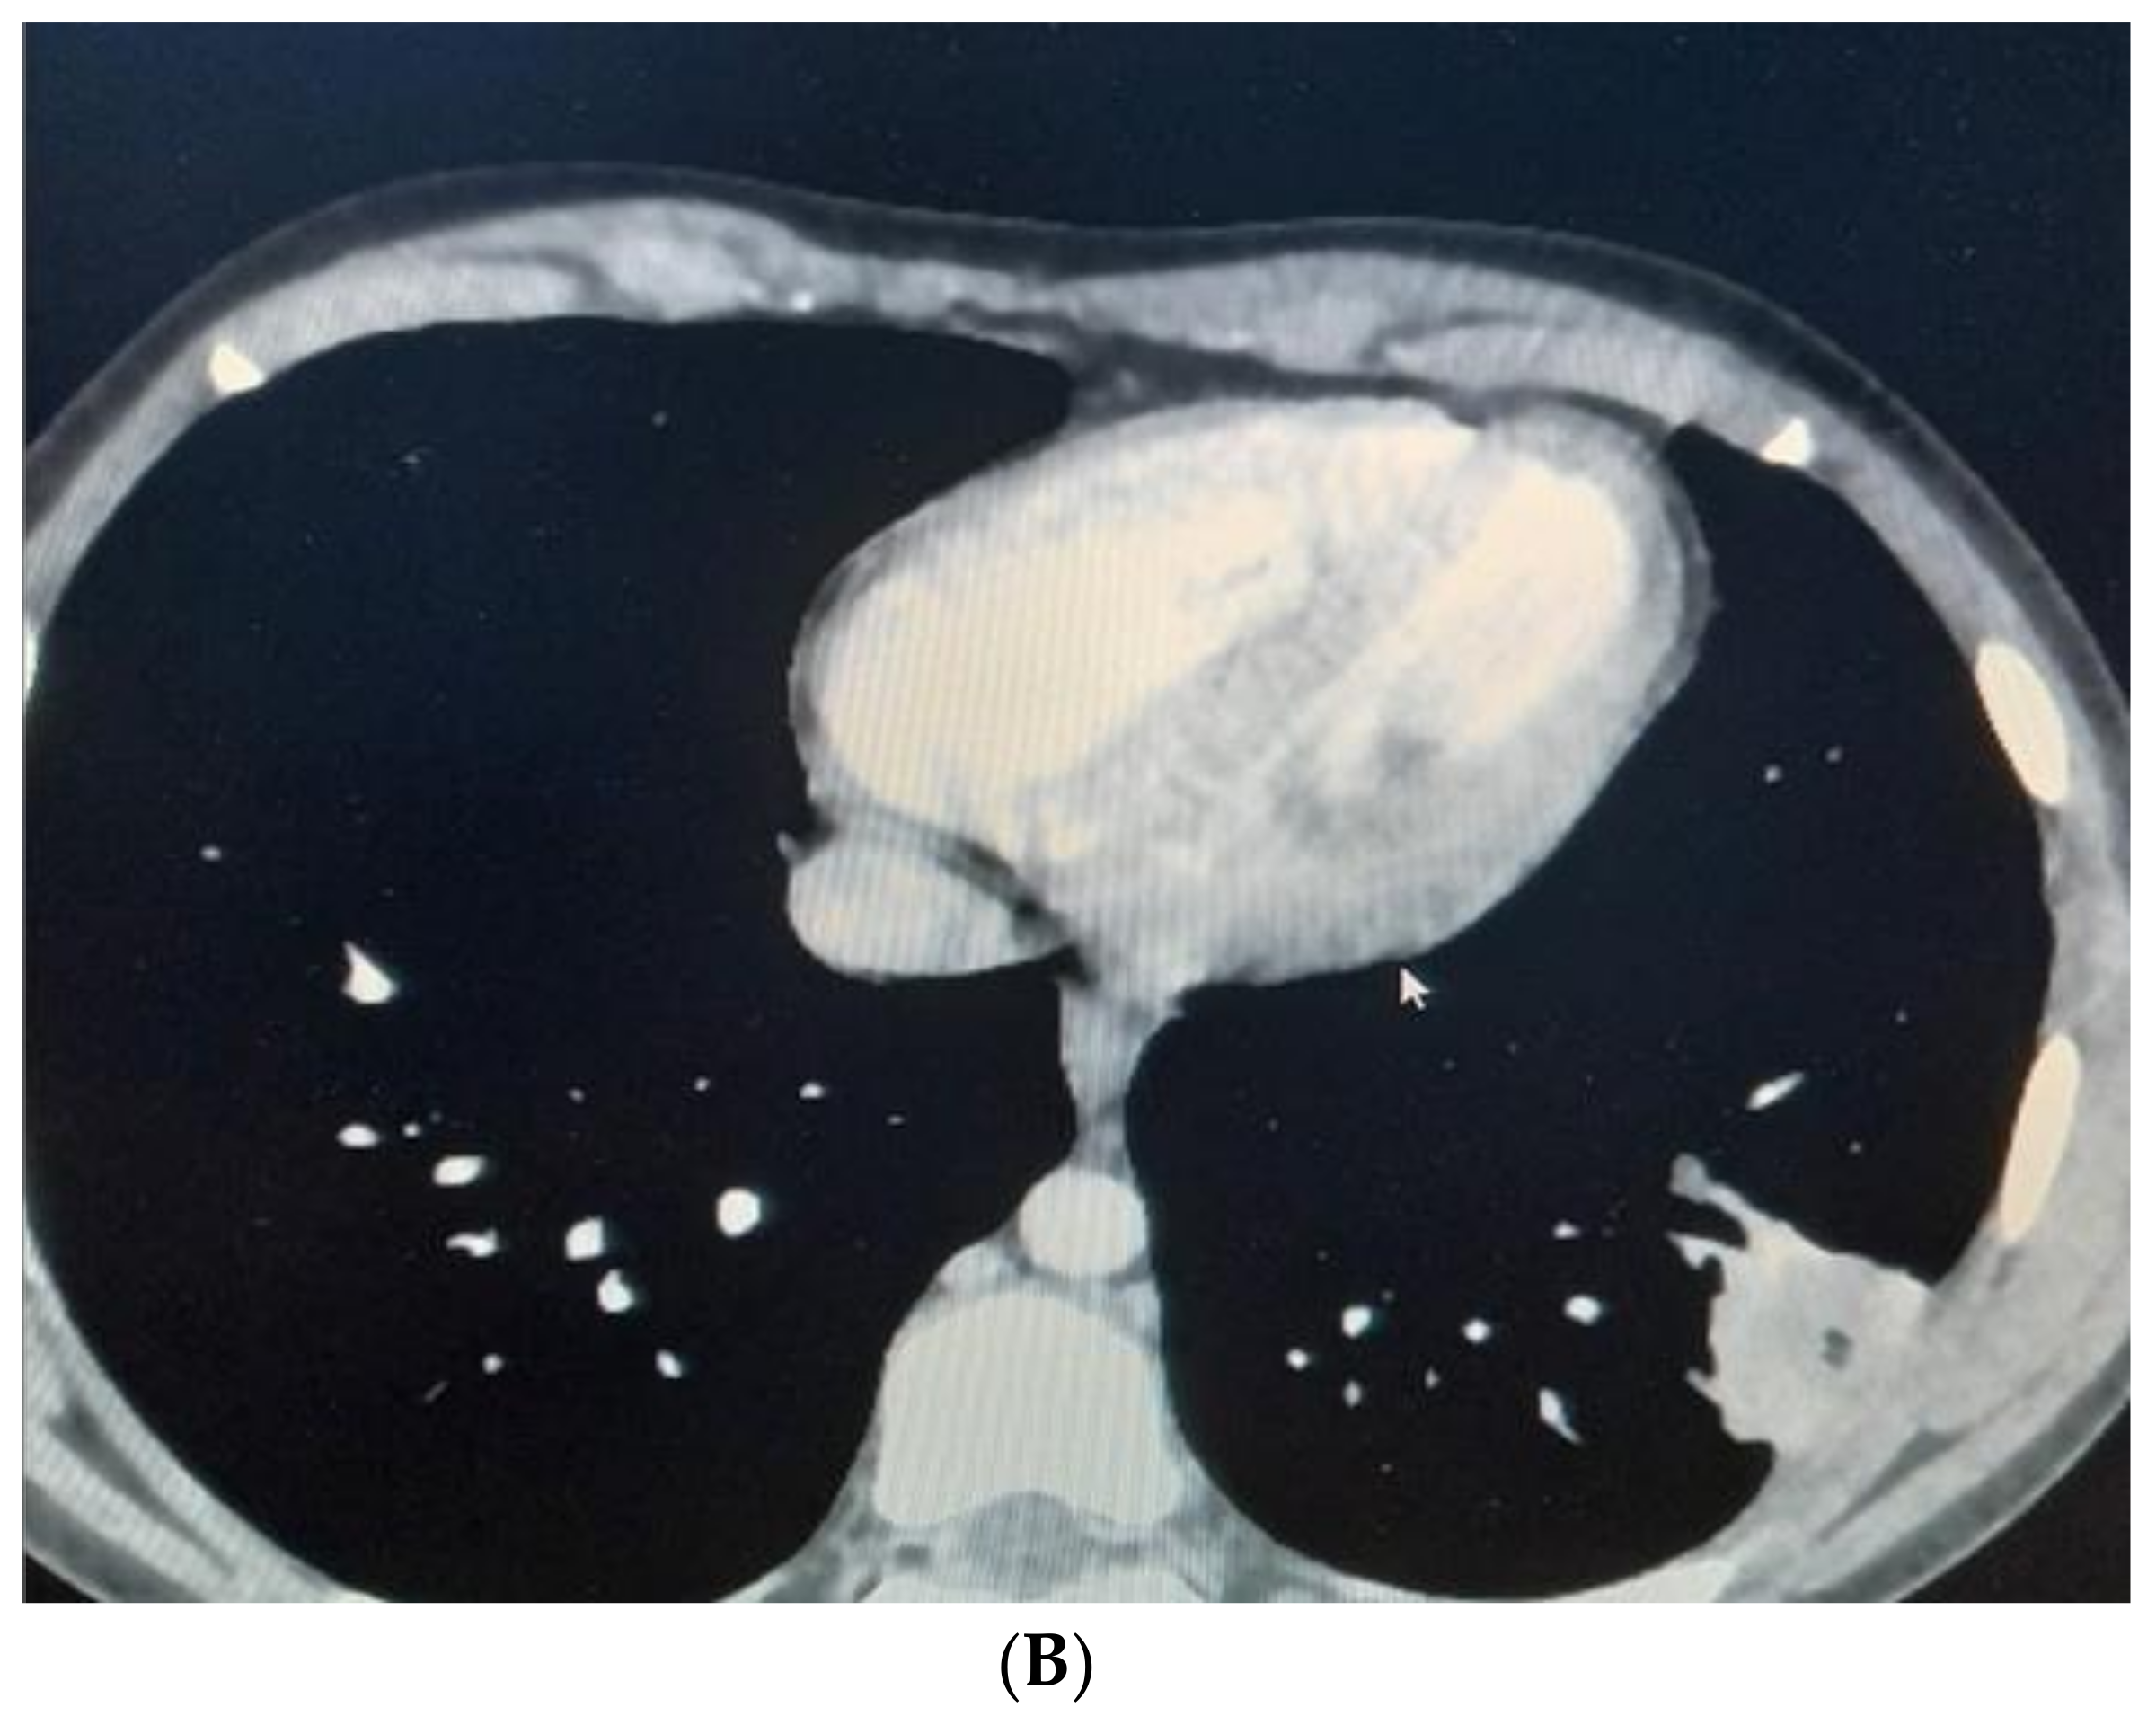

After two weeks, the child was admitted again to the Department of Pediatric Thoracic Surgery. Blood and biochemical tests were in the normal range (leucocytes 8.9 G/L, hemoglobin 136 g/L, hematocrit 0.42 L/L, thrombocytes 281 G/L, CRP 0.06 mg/dL, ASAT 26 U/L, ALAT 17 U/L, creatinine 57 µmol/L). A frontal chest X-ray revealed the persistence of the radiological findings from the last stay (Figure 3). A CT scan showed a zone of consolidation and a typical view of a lung abscess in the left posterior basal segment (Figure 4A,B). Then, the decision for surgery was taken. A left-sided VATS was performed. An abscess (3 cm/4 cm/5 cm) was found in the 10th segment, and an atypical lung resection was performed. After the procedure, the lung specimen was cut, and a foreign body (an awn from the species Hordeum murinum) was found (Figure 5A,B). A 20 Ch drain tube was inserted into the pleural cavity. After the surgery, the improvement was marked. Perioperative and postoperative therapy comprised Sultamicillin, Cefoperazon/Sulbactam, Clindamycin, and postoperative analgesia. The postoperative period was uneventful. The patient was discharged on the 9th postoperative day.

Figure 4. (A). CT scan showing lung abscess in left posterior basal segment—a coronal view. (B). CT scan—an axial view.